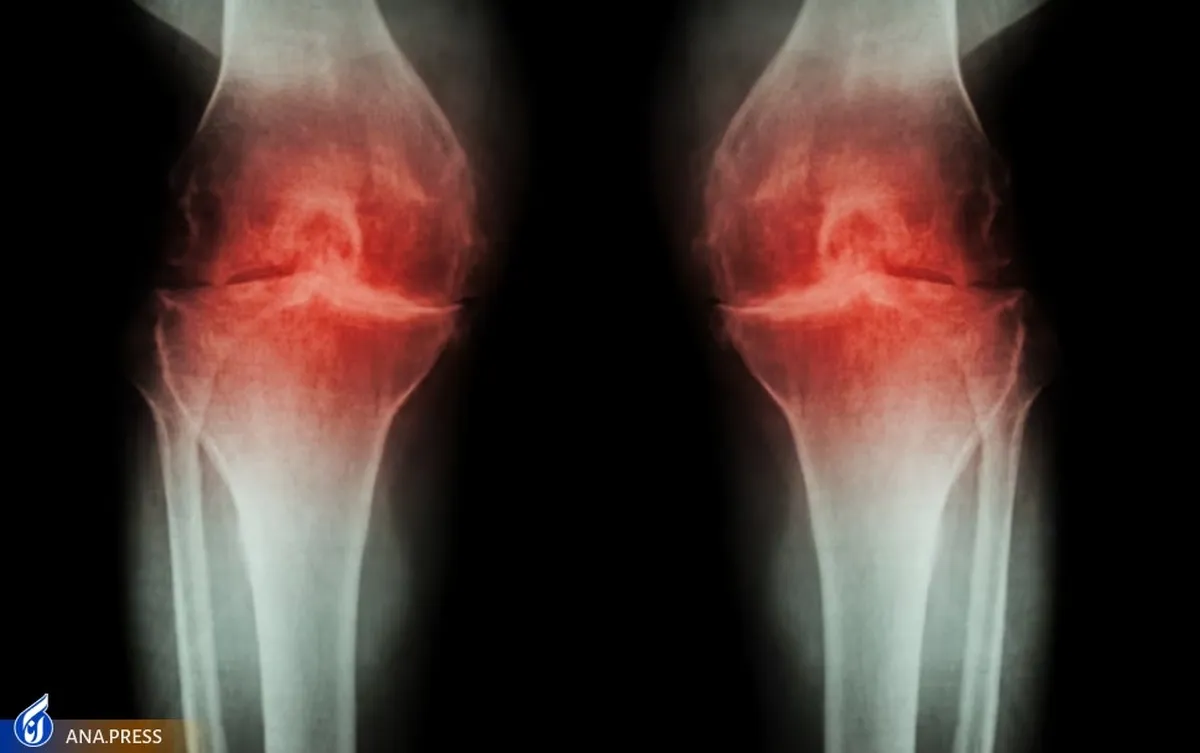

این پژوهش جدید که با رهبری یوهانا لویتجنس از دانشگاه کالیفرنیا، انجام شده بر ارتباط بین استفاده طولانی مدت از داروهای ضدالتهاب غیر استروئیدی و یک علامت آرتریت به نام سینوویت متمرکز است. غشای سینوویال بافت همبندی است که مفاصل را مانند زانو یا مچ دست در بر میگیرد و سینوویت زمانی اتفاق میافتد که آن غشاء تحریک و ملتهب میشود.

در این مطالعه محققان بیش از 1000 فرد مبتلا به آرتروز زاتو متوسط تا شدید را انتخاب کردند. حدود یک چهارم از گروهها برای بیش از یکسال درمان مداوم NSAID دریافت کردند، در حالی که بقیه شرکتکنندگان با مسکنهای رایج درمان نشدند. هر یک از شرکت کنندگان در ابتدای مطالعه، و دوباره چهار سال بعد، MRI زانو انجام دادند.

با ارزیابی MRI بیماران، محققان در طوب دوره چهارساله مطالعه هیچ مزیت بلندمدتی از استفاده از داروهای ضد التهابی مشاهده نکردند. در واقع، نشانگرهای التهاب مفاصل در گروهی که داروهای ضدالتهاب مصرف میکردند به طور غیرمنتظرهای بدتر از افرادی بود که داروهای ضد التهاب مصرف نمیکردند.